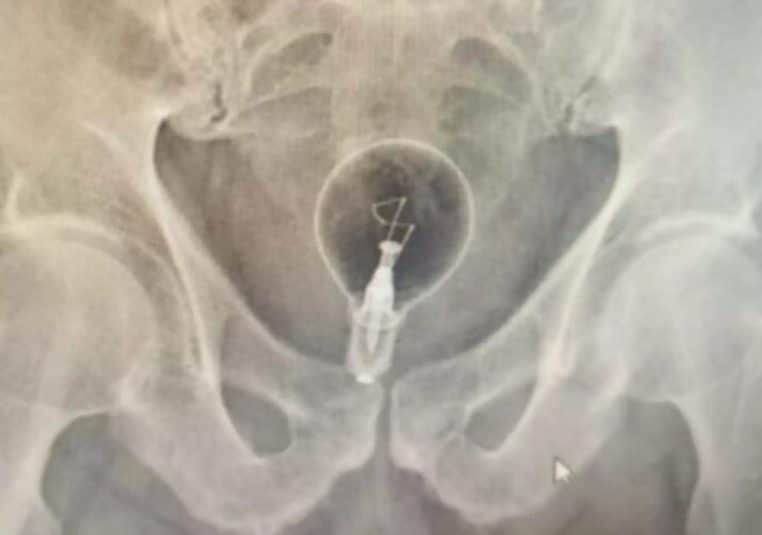

Alertée par la scène, la fille a immédiatement appelé les secours. Arrivés sur place, les ambulanciers ont rapidement compris qu’un corps étranger se trouvait dans l’organisme du patient. Et à la surprise générale, il s’agissait… d’une ampoule électrique.

À l’hôpital, les médecins ont confirmé que l’ampoule était restée intacte, mais coincée depuis plusieurs heures. L’homme, trop gêné pour expliquer comment elle s’était retrouvée là, a fini par avouer qu’il avait tenté de la retirer lui-même avec un tournevis, ce qui a aggravé les lésions internes et provoqué des saignements importants.

Grâce à une endoscopie, l’équipe médicale est parvenue à retirer l’ampoule sans la briser. Le patient est désormais en observation au service de chirurgie et son état est jugé stable.